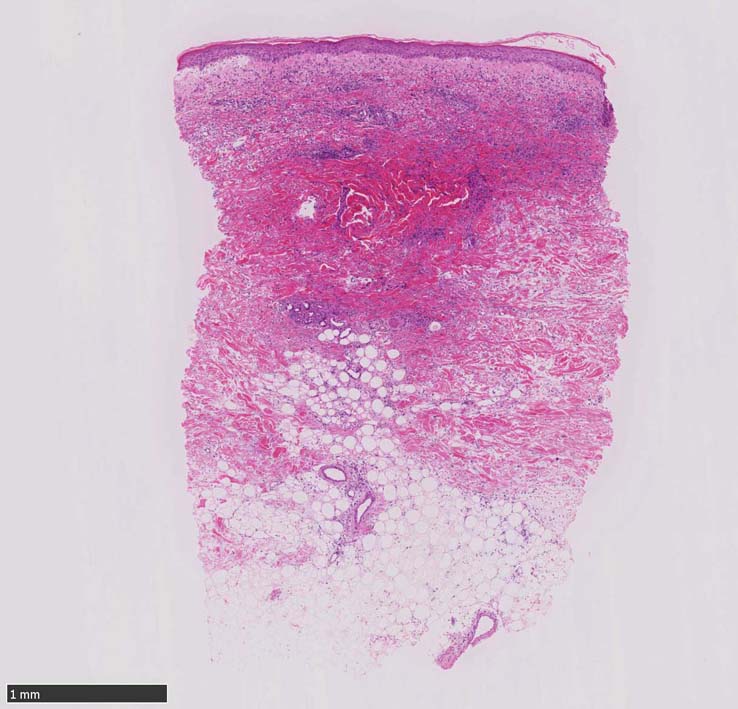

HE x40. Sweet病最盛期皮膚病変の所見があります.

表皮下水疱, 真皮上層の細血管周囲に密な好中球浸潤あり.(thumb nail clickで大きなphotoが見られます)

HE x40. 表皮下水疱あり. 真皮上層は浮腫状. 真皮から皮下組織にかけて, 多数の好中球が浸潤している. リンパ球, 好酸球が混在, 核破砕物を貪食するマクロファージが増加. 膠原線維にはところどころ変性が見られる.

真皮上層には核破砕物が多く, 好中球浸潤が認められる. 慢性炎症性細胞も浸潤している.

フィブリノイド壊死を呈する血管炎は認められない.

皮下脂肪織炎病変には局所的なhemophagocytosisが認められる. 血管にはfibrinoid necrosisは見られない。